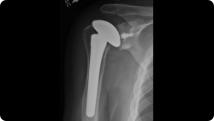

Radiographic image of shoulder arthritis Radiographic image of a total shoulder replacement

Shoulder Arthritis

Total Shoulder Replacement